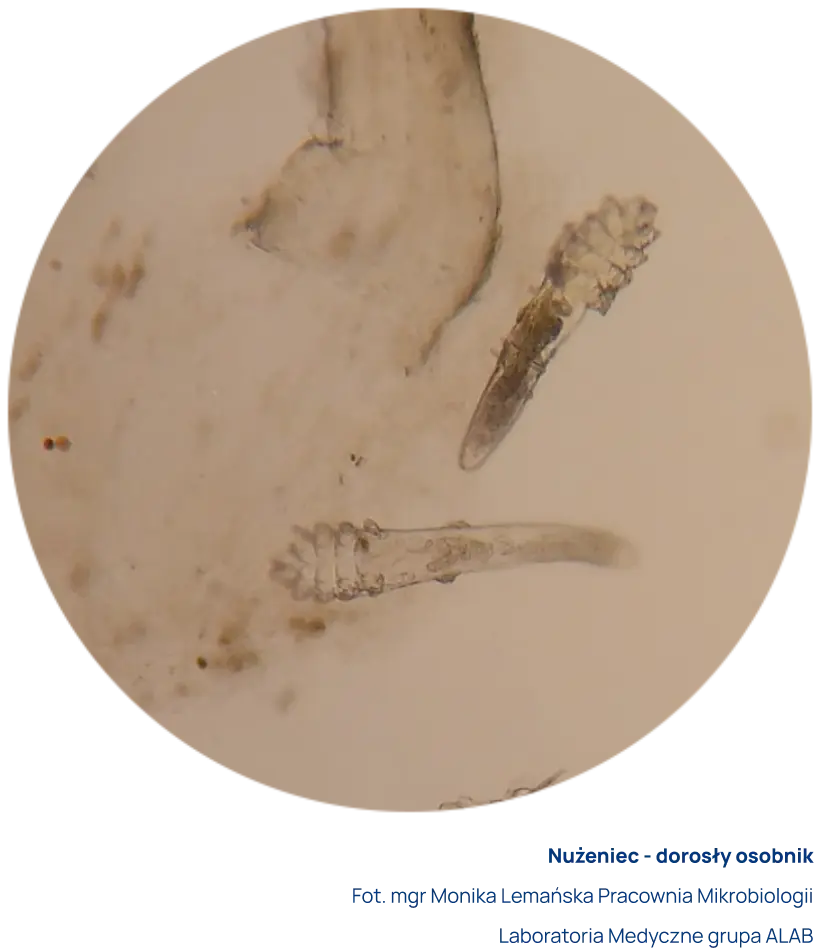

Do badania pobiera się za pomocą pincety rzęsy z obu oczu. Rzęsy umieszcza się w specjalnym płynie. Preparat mikroskopowy ogląda się bezpośrednio po pobraniu z użyciem mikroskopu świetlnego w powiększeniu x20. Dopuszczalny jest transport z Punktu Pobrań do Laboratorium w jałowym suchym pojemniku.

Za dodatni wynik uznaje się obecność w preparacie postaci dorosłych, larwalnych i/lub jaj nużeńca z jednoczesnym występowaniem objawów klinicznych